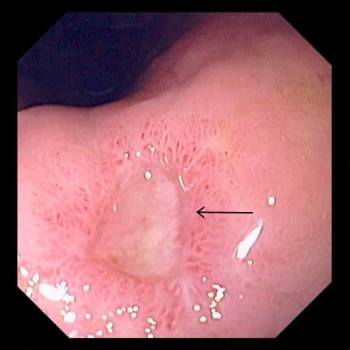

위장의 위산과 소화효소는 위 속의 음식물을 소화하기 위해 필요한 중요한 역할을 하지만, 위장 점막 역시 이로 인한 손상을 입을 수 있다. 그렇기 때문에 위장에는 위 점막을 보호하기 위한 방어인자가 존재하며, 건강한 위장에서는 위산과 같은 공격인자와 방어인자가 균형을 이루고 있다. 이 공격인자와 방어인자 간의 균형이 깨져 점막을 넘어 깊숙이까지 손상되는 경우 소화성 궤양이 발생한다.

소화성 궤양의 가장 주요한 원인 중 하나는 헬리코박터 파일로리 균 감염이다. 헬리코박터 파일로리 균은 산성이 높은 위장에서 살아남기 위해 다량의 암모니아를 만들어 산을 중화시킨다. 이 과정에서 발생하는 암모니아와 세균으로 인한 독성 물질이 위 점막 손상과 염증 반응을 일으킨다.

소화성 궤양 환자는 아무 증상이 없을 수도 있으나, 일반적으로 속 쓰린 증상을 느끼는 경우가 많다. 십이지장 궤양인 경우 식후 1~3시간 또는 공복 시에 상복부 통증이 나타나는 경우가 많고, 위 궤양의 경우 음식물에 의해 통증이 악화된다고 알려져 있으나 증상만으로 이를 감별하기는 어렵다. 이 외에도 더부룩함, 소화불량, 식욕부진, 구토 등이 나타날 수 있고, 궤양환자 중 약 15%에서 위장관 출혈이 나타난다.